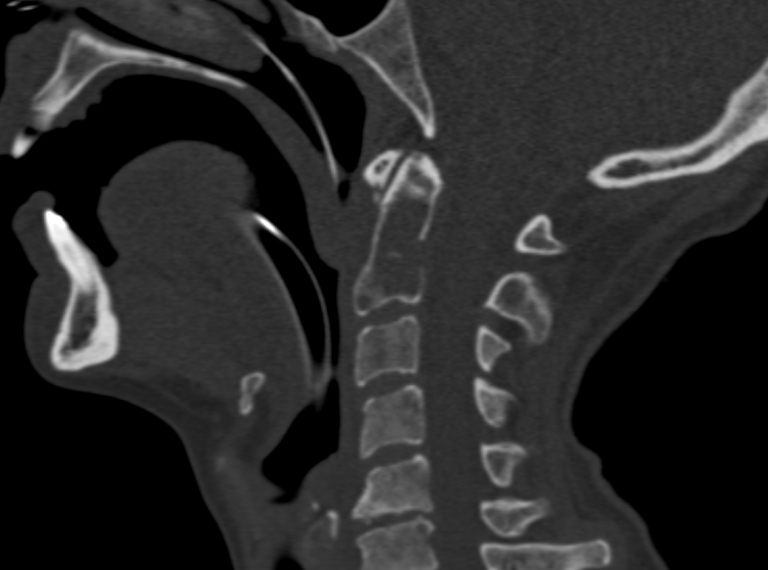

L’ostéosynthèse de la dent de C2 par voie percutanée latéro-cervicale est une technique innovante, peu répandue en France et non réalisée jusqu’alors en Auvergne. Elle a été démocratisée par des équipes lyonnaises et parisiennes, et se distingue par son efficacité clinique et un faible taux de complications.

L’intervention se déroule en salle de radiologie interventionnelle, sous anesthésie générale. Grâce à un guidage scanner et scopique en continu, une précision millimétrique est assurée à chaque étape :

• Hydrodissection cervicale : injection de sérum physiologique pour écarter les structures à risque (artère carotide, veine jugulaire, trachée).

• Mise en place de la vis : introduction d’un trocart osseux, puis d’une broche et enfin d’une vis canulée adaptée à l’anatomie du patient.

• Cimentoplastie complémentaire : injection de ciment acrylique dans la lésion pour renforcer la consolidation et la stabilité de la vis.

Quelques images de l'intervention...